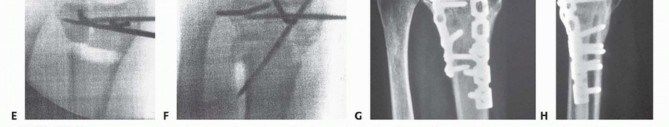

### TECH FIG 2 • A. Kirschner wires are placed parallel to the articular surface. Fluoroscopic image showing pin placement. B. The osteotomy is made with a saw as close as possible to the original fracture site. C. Lateral fluoroscopic image showing use of a lamina spreader to realign the distal fragment. D. The osteotomy has been opened and is ready for graft placement. (Copyright Diego Fernandez, MD, PhD.) A distractor or small external fixator may facilitate realignment and provisionally stabilize the fracture. The proximal threaded pin is drilled into the radial diaphysis perpendicularly in a position that will not interfere with implant application. The distal threaded pin is drilled at an angle equal to the desired correction of the lateral tilt of the distal radius articular surface so that distraction of the two pins will bring this pin parallel to the proximal pin (perpendicular to the radius), thereby restoring alignment. The pins should be drilled so that they also help restore the appropriate ulnarward inclination of the distal radius articular surface when distracted. Planned angular corrections can be monitored with sterile geometric templates. The osteotomy is made parallel with the distal Kirschner wire and as close to the original fracture site as possible using an oscillating saw ( TECH FIG 2B). If the fracture is not yet completely healed (nascent malunion— usually within 4 months of injury), recreate the original fracture line by carefully removing fracture callus at the fracture site. This callus can be saved and used as bone graft. If the fracture is solidly healed, attempt to identify the prior fracture site. If this is uncertain, choose a site that creates a distal fragment large enough to facilitate manipulation and internal fixation while trying to stay distal enough to take advantage of the healing capacity of metaphyseal bone. A lamina spreader can be used to help realign the distal fragment as well ( TECH FIG 2C,D). Care must be taken when operating on osteoporotic bone. Additional provisional stability can be provided by placing 1.6-mm smooth Kirschner wires. If the ulnar variance can be restored with angular realignment alone, the volar cortex can be cracked and hinged open in an attempt to maintain some stability of the osteotomy. If lengthening of the volar cortex is required to restore ulnar variance, a second distractor in another plane (eg, direct radial) may prove useful for obtaining and maintaining alignment. ### Graft Insertion and Fixation Once the osteotomy is created and the radius realigned, bone graft is inserted. Harvest bone graft ( TECH FIG 3A). Either a corticocancellous (structural) bone graft or cancellous bone graft can be used. Potential advantages of a structural graft include immediate structural support ( TECH FIG 3B) and the possibility of using a smaller implant and thereby avoiding tendon irritation. A cancellous (nonstructural) bone graft can be harvested using trephines ( TECH FIG 3C). This avoids tedious, difficult, and unpredictable harvest and contouring of corticocancellous grafts as well as the morbidity associated with harvest of a standard iliac crest bone graft. Apply a single T- or Pi-shaped plate or two 2.0- or 2.4-mm plates (one applied dorsally, ulnar to the tubercle of Lister, and 147 the other applied radially between the first and second dorsal compartments).

### TECH FIG 3 • A. Corticocancellous bone graft is harvested from the iliac crest. B. After final sculpting, it is applied to the osteotomy site. C. Autogenous cancellous bone graft is harvested from the iliac crest using a trephine. D. A 2.0-mm condylar blade plate can provide fixed-angle internal fixation. E,F. Intraoperative photographs of the fixation. G,H. Final anteroposterior (AP) and lateral radiographs. (Copyright Diego Fernandez, MD, PhD.) When a structural, corticocancellous bone graft is used, a single plate or a plate and separate screw may be adequate ( TECH FIG 3D-H). Plates with angular stable screws or blades in the distal fragment may be more reliable than standard screws, particularly if the bone is of poor quality and if nonstructural graft is chosen. Once implants are placed and stability is ensured, remove all provisional fixation devices. This entire process is monitored using image intensification to confirm appropriate osteotomy site, correction of alignment, and implant placement. Repair the extensor retinaculum with absorbable suture. In some cases, a flap of retinaculum is brought deep to the tendons to add a layer of protection between the implants and extensor tendons. We usually do not close the retinaculum, and we no longer make retinacular flaps. The tourniquet is deflated and hemostasis ensured. The skin is closed. A bulky dressing incorporating a volar plaster wrist splint is applied. 1. ## Volar Extra-articular Distal Radius Osteotomy ### Exposure 148 Use a volar-radial Henry (flexor carpi radialis [FCR]) approach for both dorsally and volarly angulated malunions (see FIG 2C,D). Make a 5- to 7-cm longitudinal incision over the FCR tendon ending at the wrist flexion crease. If more exposure is required, the incision is angled or zigzagged at least 45 degrees toward the scaphoid distal pole. Incise the FCR sheath, retract the tendon ulnarly, and incise the floor. Leave the radial artery undissected and protected in the radial soft tissues. Sweep the fat overlying the pronator quadratus together with the digital flexors and median nerve ulnarward with a sponge or blunt elevator. Proximally in the incision, elevate the most distal aspect of the origin of the flexor pollicis longus from the volar distal radius (taking care to cauterize a consistent artery in this region) and retract it ulnarly with a small Hohmann retractor placed around the ulnar border of the radius. Expose the radial border of the radius using a blunt elevator and Hohmann retractors. Incise the pronator quadratus over its most radial and distal limits (L-shaped incision) and elevate it subperiosteally. Leaving the periosteum with the muscle can facilitate later repair. For dorsally angulated malunions, release of the radial and dorsal soft tissues facilitates realignment. The brachioradialis is Z-lengthened and the periosteum is elevated from the radius shaft proximally.

TECH FIG 4 • A-D. Realignment and provisional fixation of an extra-articular dorsally displaced malunion in the patient in FIG 2C,D. After osteotomy in the manner detailed earlier (for the dorsal approach to malunions), pronate the proximal radius shaft out of the wound, providing access to the dorsal periosteum, which can be isolated and divided. With the release of the brachioradialis and the dorsal periosteum, realignment of the radius is usually comparable to an acute fracture. Volarly angulated malunions do not need an extensive soft tissue release in most cases. The plate can facilitate realignment by pushing the distal fragments into position as the proximal screws are tightened. ### Realignment and Provisional Fixation The fragments are realigned using the techniques described earlier ( TECH FIG 4). The techniques are similar to those for acute fractures once an adequate soft tissue release has been performed. Apply a fixed-angle volar implant. Insert provisional Kirschner wires either through or adjacent to the plate (see TECH FIG 4). ### Plate Fixation Placement of the plate will frequently help reduce the proximal and distal fragments ( TECH FIG 5A,B). After final plate fixation and removal of provisional fixation, apply cancellous graft to the osteotomy site ( TECH FIG 5C-F). Excellent access is available radially for placement of the bone graft. The tourniquet is deflated and hemostasis ensured. Repair the pronator quadratus if possible. It can be sutured to the brachioradialis tendon. The skin is closed. A bulky dressing incorporating a volar plaster wrist splint is applied. 149

### TECH FIG 5 • A. Fluoroscopic image of plate fixation and realignment. B. Defect after correction. Autogenous cancellous graft (C) and graft placement (D), showing final clinical appearance. E,F. Final PA and lateral radiographs. (Copyright Diego Fernandez, MD, PhD.) -